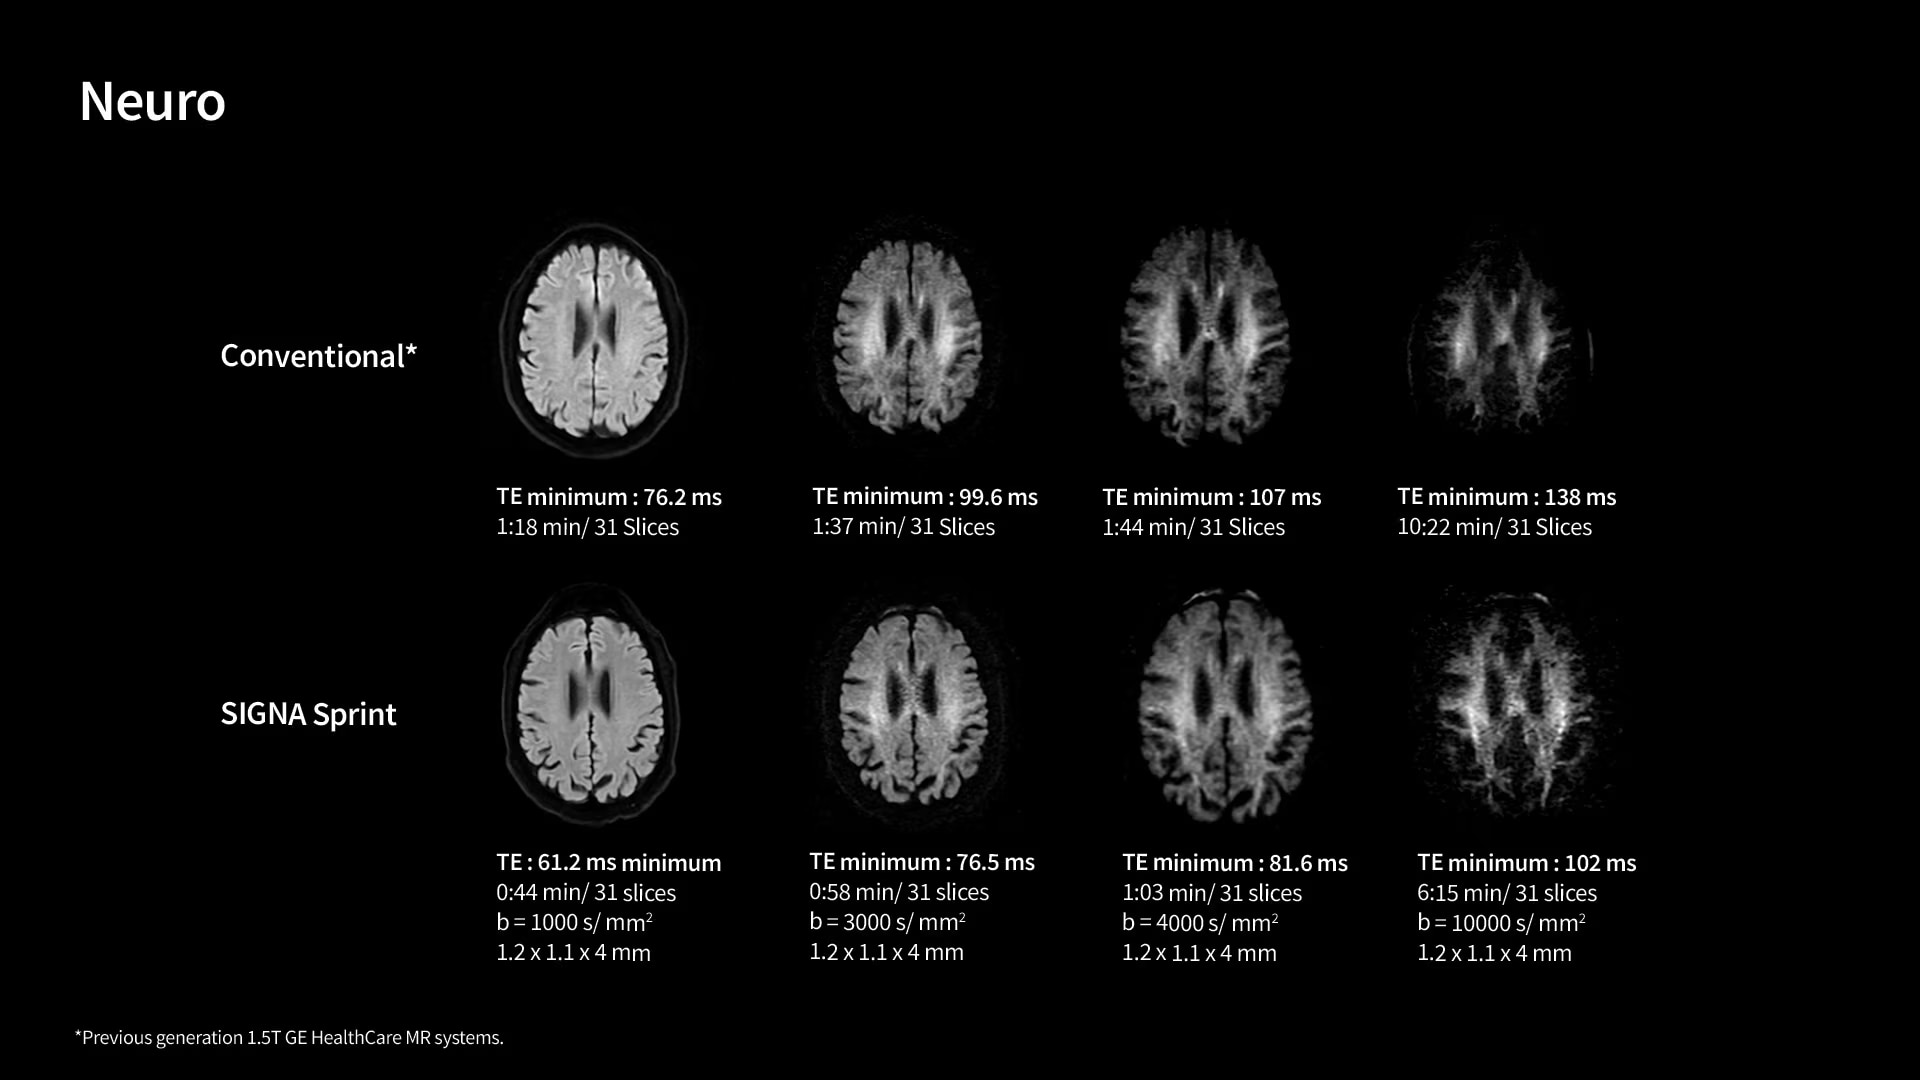

In oncological assessments, diffusion imaging is a critical clinical indicator. SIGNA Sprint offers clearer diffusion, reduced distortion, and improved SNR.¹

Within cardiovascular diseases, the functional assessment of the heart is an essential imaging application. SIGNA Sprint is powered by built-in AI technologies—Sonic DL™, AIR Recon DL and AIR x™—enabling high-quality imaging even in the most demanding anatomies.

The growing clinical need within oncology and cardiology requires an MRI scanner that can rise to the challenge. With a high gradient performance of 65/200, SIGNA Sprint helps deliver crystal-clear imaging for ultimate diagnostic confidence. Improved signal-to-noise ratio (SNR) and diffusion, with deep-learning solutions that could enhance diagnostics and treatment response monitoring in your oncology patients.¹ Additionally, the shift from qualitative to quantitative cardiac MRI reduces the time and expertise needed to interpret scans and offers greater consistency and reliability. Helping you to unlock the power to explore further - even in your most challenging cases.